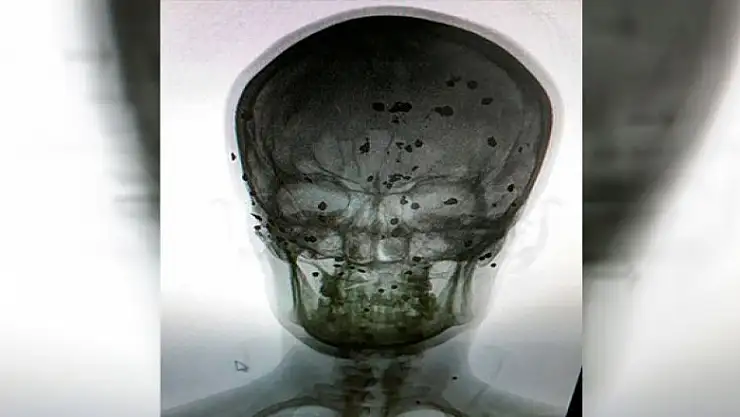

Batman'ın Sason ilçesine 13 yıl önce misafirliğe gittiği akrabasının temizlediği tüfeğinin kazara ateş alması sonucu yaralanan Cuma Araz (30), başındaki 80 saçma ile hayatını sürdürüyor.

Sason ilçesine bağlı Dereiçi köyünde yaşayan 4 çocuk babası Cuma Araz, 2005 yılında Altıdere köyündeki akrabasını ziyarete gitti. Akşam saatlerinde sohbet sırasında akrabasının temizliğini yaptığı av tüfeği, kazada ateş aldı. Tüfekten çıkan saçmalar, Cuma Araz'ın başına isabet etti. Ağır yaralanan Araz, kaldırıldığı Diyarbakır Dicle Üniversitesi'nde uzun süre tedavi gördü.

Burada çekilen röntgeninde tek tek görülen saçmalarla 13 yıldan beri yaşamak zorunda kalan Araz, "Bugüne kadar doktorlar hiç ameliyat etmedi. Bana, kafamda bulunna 80 saçmanın bir zararının olmadığını söylediler. Saçmalardan iki tanesi, kafatasımı delerek beyin zarında takılıp durduğunu söylediler. İki tanesi ise ses tellerime zarar verdi. Artık vücudumdaki bu saçmalardan kurtulmak istiyorum. Bu konuda yetkililerin bana destek olmasını istiyorum" dedi.